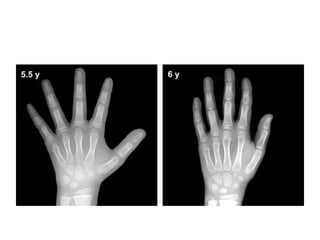

Pre-puberty

• Females: 2 years to 7 years of age

• Males: 3 years to 9 years of age

• Assessments of skeletal maturity in pre-pubertal

children are primarily based on the

epiphyseal size of the phalanges as they relate

to the adjacent metaphyses

• During this stage of development, the ossification

centers for the epiphyses increase in width and

thickness, and eventually assume a transverse

diameter as wide as the metaphyses.

• More weight is given to the size of the epiphyses

in the distal phalanges than to that in the middle

phalanges, and even less to that in the proximal

phalanges

• Depiction of the

progressive growth of

the width of the

epiphyses, which,

during this stage of

development, become

as wide as the

metaphyses

• The epiphysis of the ulna and all carpal bones,

with the exception of the pisiform, usually

become recognizable before puberty.

• However, these ossification centers, like those

of the metacarpals, are less reliable indicators

of bone age at this stage of life.